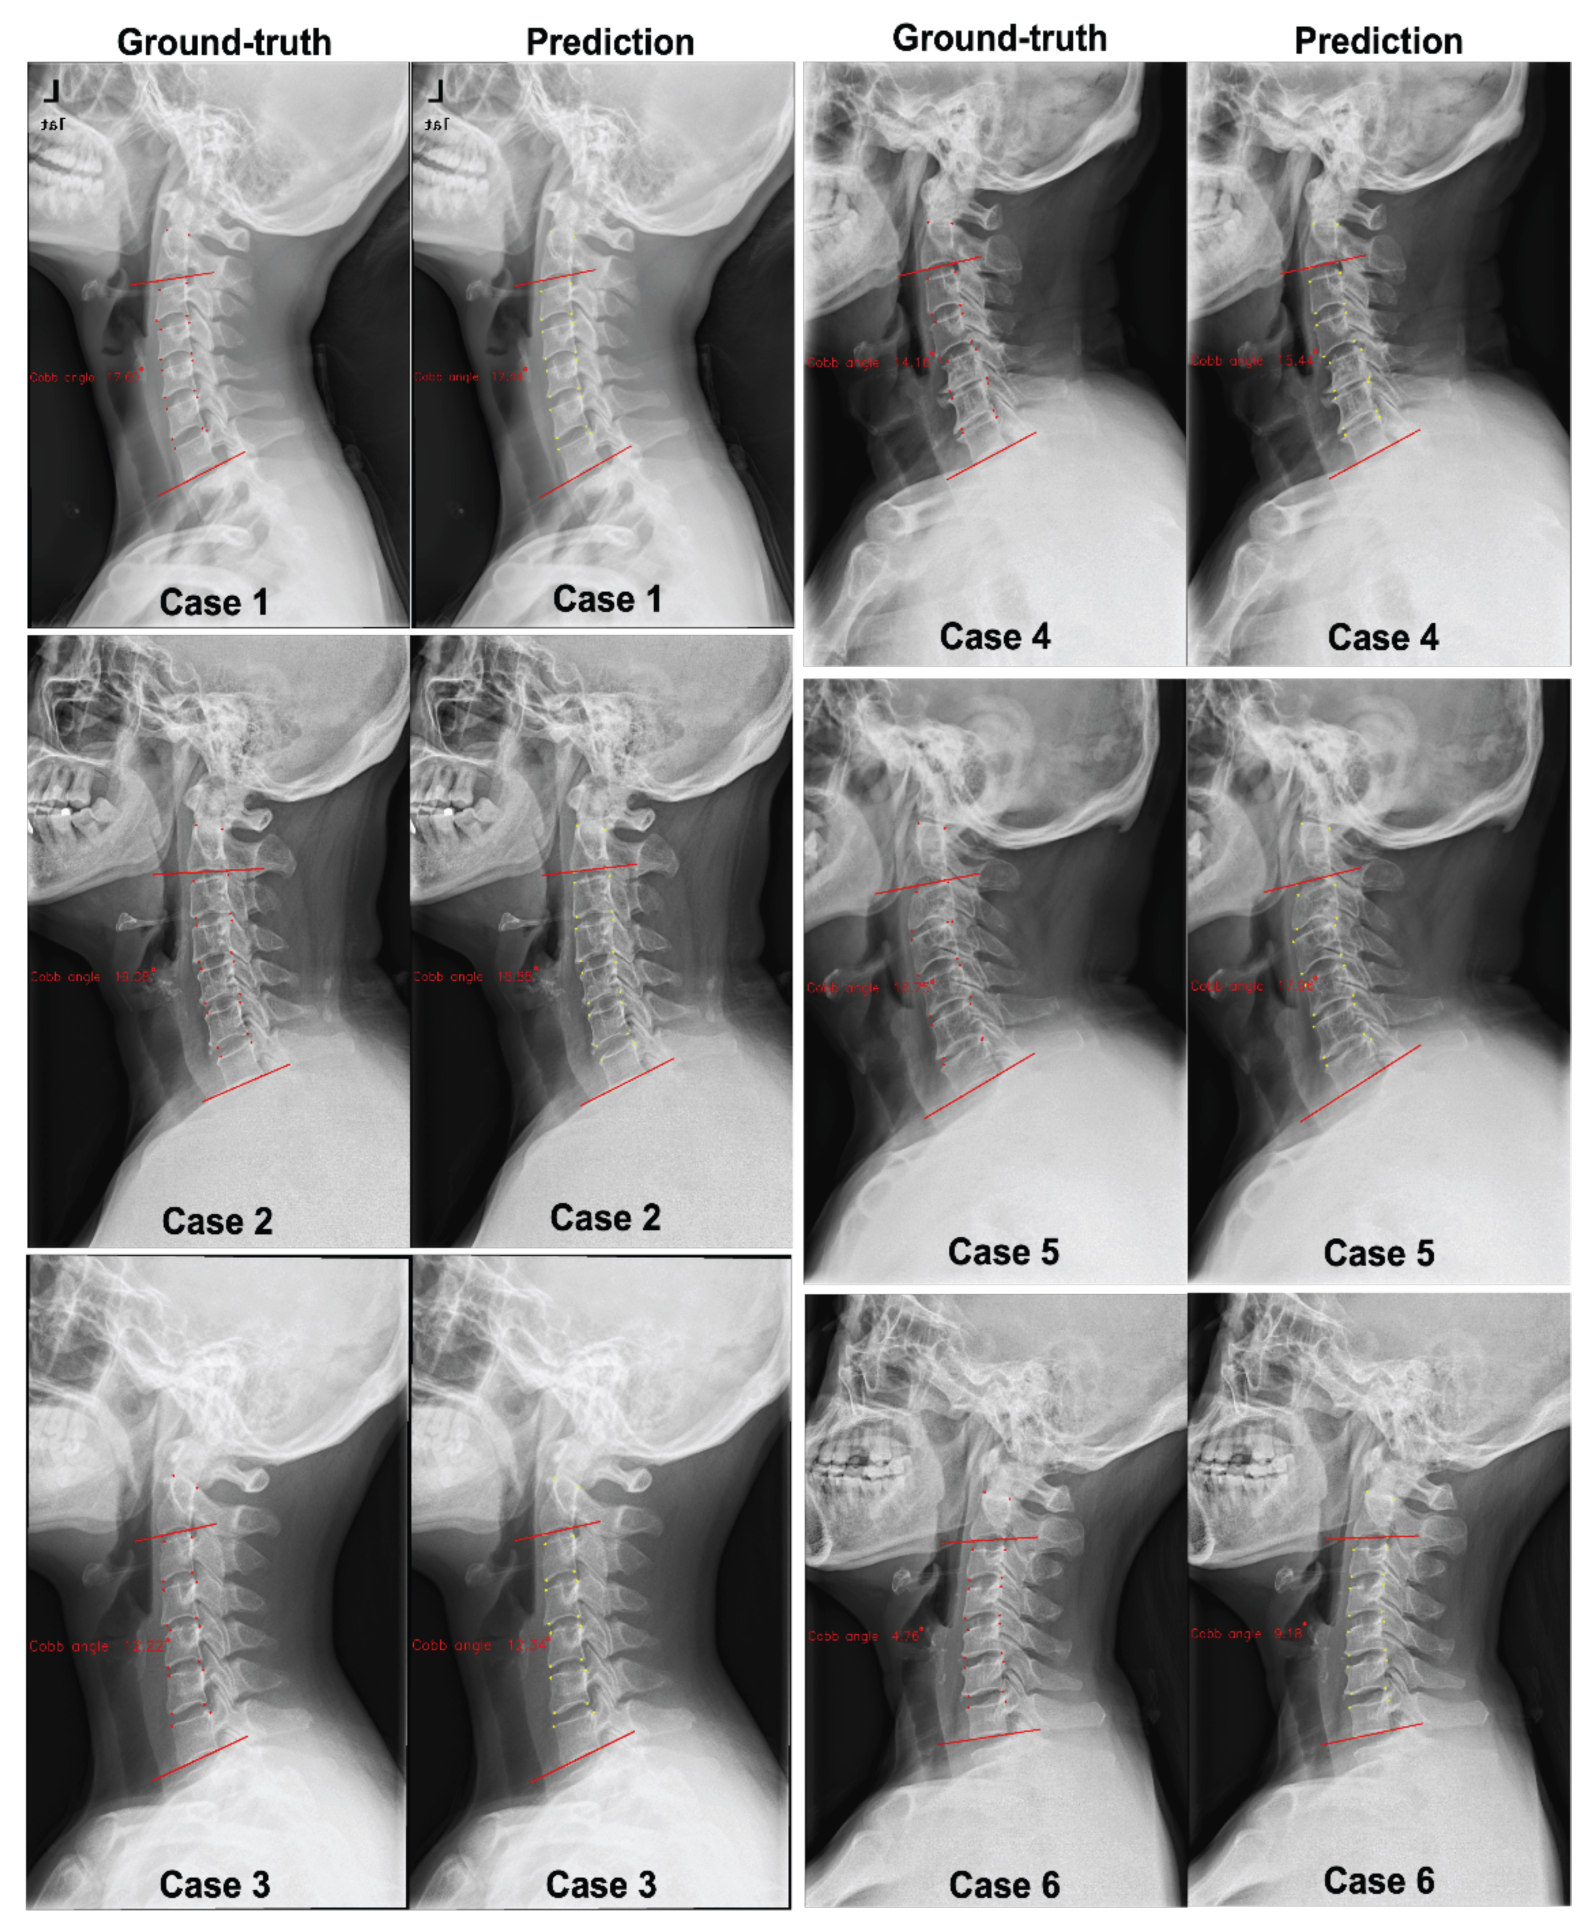

Two datasets are used to evaluate the superiority of our proposed method: our dataset and the public AASCE MICCAI 2019 challenge dataset. Figure 1 shows a few samples with corresponding landmarks of these two datasets. More details are presented as follows:

CS799 dataset: Our dataset contains a total of 799 LAT X-ray images of the cervical spine. All the samples were captured from 799 distinct human subjects. The subjects in this dataset exhibit a wide age distribution (from 12 to 84 years), and the average age is 45.3 years. The curvature of the cervical spine is also diverse. The Cobb angles are distributed between 0° and 46.3°. The cervical spine has a unique vertebral appearance. All images were collected by Shanghai ChangZheng Hospital, annotated, and proofread by spine surgery specialists. The minimum resolution of the picture is 1217 × 1779, while the maximum resolution is 1916 × 2695. We trained our models on the training dataset with 559 images (75%), of which 159 images were used for validation (15%), and 81 images werew used for testing (10%). Each image includes 24 landmarks.

AASCE MICCAI 2019 challenge dataset: Each X-ray image has 68 landmarks corresponding to 17 vertebrae. Each vertebra includes four corner landmarks (top-left, top-right, bottom-left, and bottom-right). The challenge also supplies Cobb angles for proximal thoracic (PT), main thoracic (MT), and thoracolumbar (TL). In the same way as the data was split in [9], we divided the dataset into three parts: 348 images for training (60%), 116 images for validation (20%), and 116 images for testing (20%).

Figure 1. Samples from our dataset CS799 (a,b), and the AASCE MICCAI 2019 challenge dataset (c,d). The yellow points represent landmarks marked by experts.

In addition, it is necessary to discuss the influence of illumination on the experimental results to ensure the reliability of computer-aided diagnosis results. The impact of lighting problems on computer-vision tasks is expounded in [30]. In this work, the mean absolute error was 3.64° for the AASCE2019 dataset and 1.79° for the CS799 dataset. From analyzing the lighting situation in the dataset, one reason for the smaller average error on the CS799 dataset may be because the image lighting situation in CS799 is more stable than that in AASCE2019. Most of the images in AASCE2019 are shown in Figure 1c,d, with significant changes in illumination. While the CS799 images are shown in Figure 3, the changes in illumination are not obvious. For these two different tasks, the goal is the same. Their goal is to find the optimal algorithm to reduce the error of Cobb angle estimation. For AASCE2019, another requirement is that the algorithm should be robust against noise and lighting changes; this means that the AASCE2019 dataset has higher requirements for the algorithm.